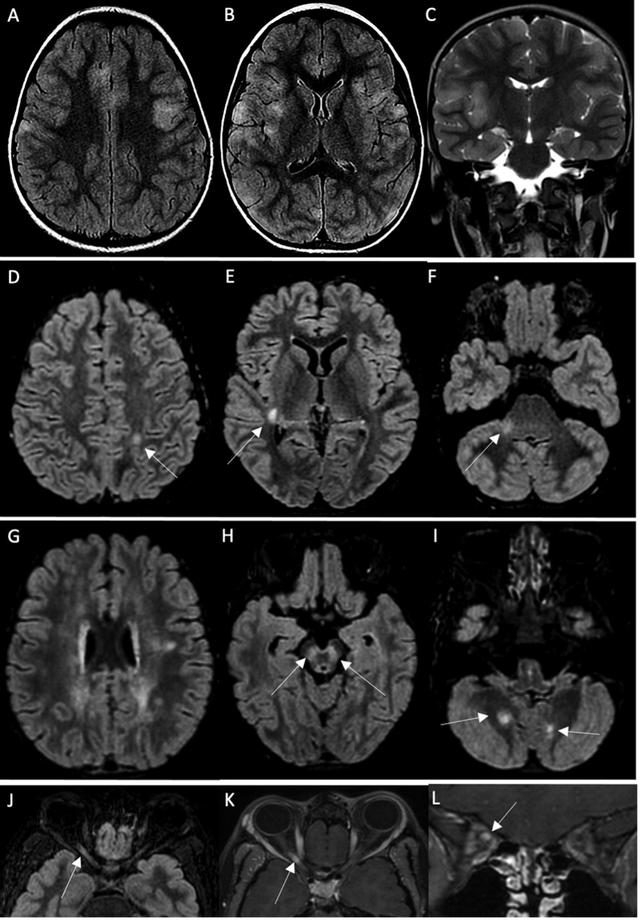

19名患者中有14名MRI异常。4例MRI显示ADEM伴有多灶性脑损伤,1例伴有视神经炎;3例显示胼胝体细胞毒性病变(CLOCC综合征),胼胝体压部扩散受限,T2-FLAIR高信号,2例小脑炎;1例分别显示孤立性视神经炎、孤立性面神经炎和多发性神经炎。19例脊柱MRI中有5例异常:5例显示脊髓炎,其中3例与ADEM相关,1例为孤立性,1例与马尾神经根的对比增强相关。所有脊髓炎病例均显示超过3个椎体受累。

10名测试儿童中有4名的血清中抗MOG(髓鞘少突胶质细胞)和抗AQP4(水通道蛋白4)抗体呈阳性。AQP4主要临床意义在于诊断视神经脊髓炎。MOG的糖蛋白是髓鞘膜和少突胶质细胞表面最外层的膜蛋白,是导致多发性硬化(MS)脱髓鞘的关键成分,针对MOG的抗体能够在体内和体外造成脱髓鞘。

一名抗AQP4抗体阳性的女孩14岁,无既往明显病史,她有单独的右眼视觉症状,其他神经系统检查正常,临床诊断为视神经炎,脑部MRI显示视神经炎无脑部或脊柱异常。其他3名抗MOG抗体阳性的儿童分别为1.5岁、4岁和10岁,其中男孩2人。这3例病例均未出现MIS-C症状,二十出现神经系统症状(2人共济失调,1人癫痫发作、意识丧失、面瘫和偏瘫)。其中的第3名患者进入重症监护室。